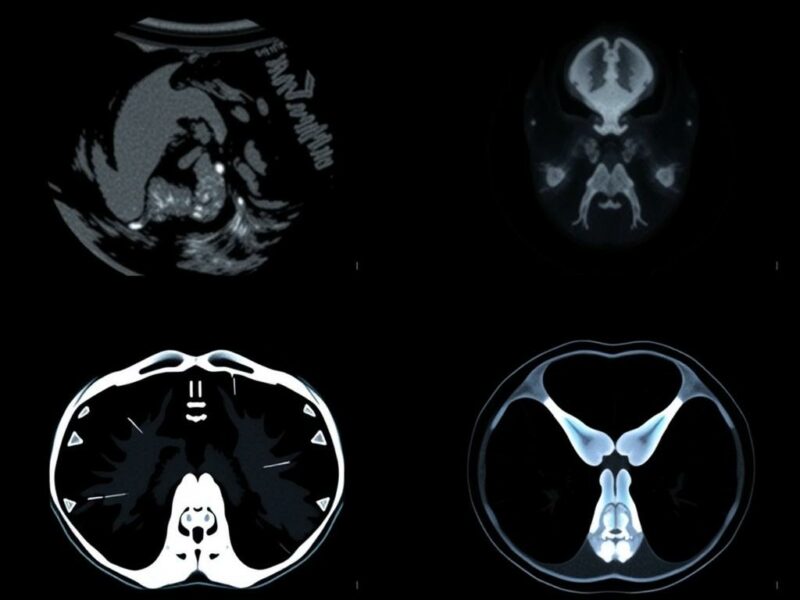

La RM tiene ventajas claras que hacen que, en muchos contextos, sea la opción diagnóstica preferente. Primero, ofrece una resolución de contraste superior: distingue mejor entre tejidos de características similares que otros métodos no separan con tanta claridad. Esto la hace excelente en neurología para evaluar el cerebro y la médula, en ortopedia para ver meniscos y ligamentos, en oncología para caracterizar masas y planificar tratamientos, y en cardiología para evaluar miocardio y grandes vasos.

Tercero, la RM permite realizar estudios funcionales y de perfusión, mapear fibras nerviosas (tractografía), y cuantificar procesos fisiopatológicos con técnicas avanzadas que no están disponibles en tecnología como la ecografía. En el contexto del embarazo, estas capacidades se traducen en diagnósticos más precisos de malformaciones fetales, placentarias o maternas, en la evaluación de eventos cerebrovasculares en la madre, y en la valoración de patologías torácicas o abdominales que comprometen la salud materna.

Consideremos unos ejemplos prácticos que muestran cuándo la RM puede cambiar el rumbo clínico. Imagina una ecografía fetal que sugiere una lesión cerebral pero no logra definir si se trata de un quiste benigno o una malformación cortical compleja; la RM fetal puede aclarar el diagnóstico y ayudar a explicar el pronóstico y las opciones obstétricas. Otro ejemplo: una mujer embarazada con dolor abdominal agudo y pruebas de laboratorio alteradas donde la ecografía no muestra la causa; una RM abdominal puede detectar torsión ovárica, apendicitis no evidente o una hemorragia intraabdominal que requiera intervención urgente. En caso de placenta previa con sospecha de invasión placentaria, una RM placentaria bien protocolizada aporta información sobre profundidad de invasión y cercanía a estructuras vasculares, lo que es vital para planificar un parto seguro.